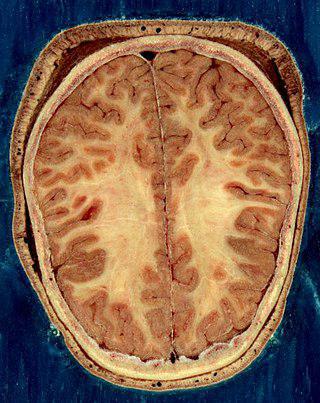

Ошибочно считать, что чем больше этот орган (на фото), тем лучше.

Головно́й мо́зг челове́ка является органом центральной нервной системы, состоящей из множества взаимосвязанных между собой нервных клеток и их отростков.